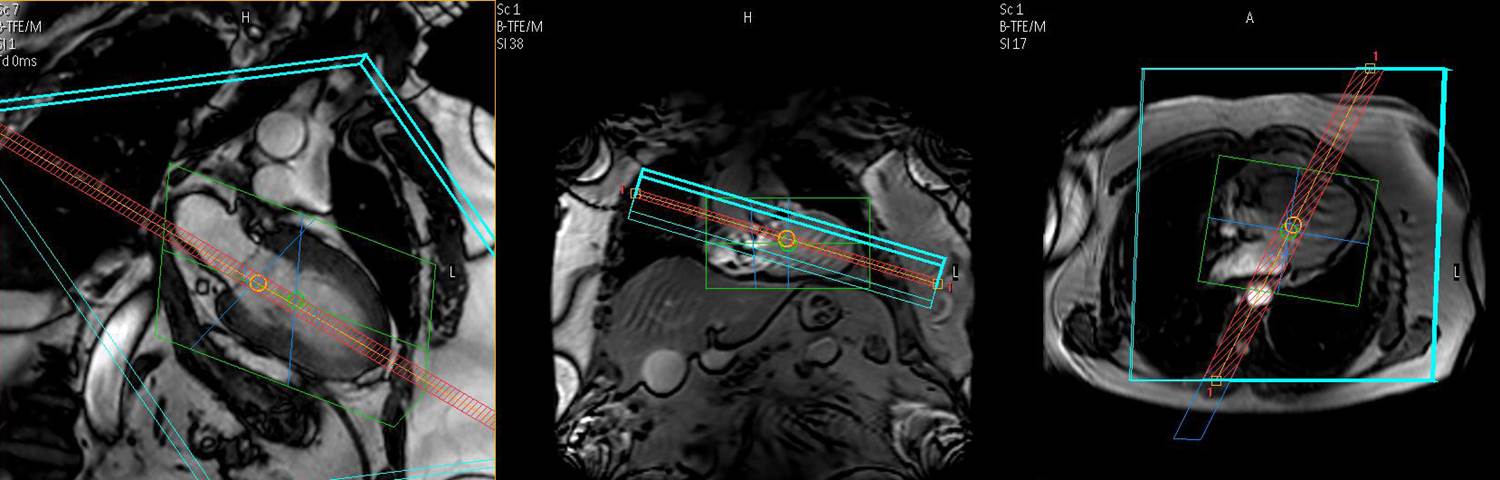

Workshop: Kardiales Mapping T1, T2 und T2*

Dieser Workshop bietet spezielles Training über die Prinzipien und Anwendungsmöglichkeiten der quantitativen Gewebecharakterisierung mittels T1, T2 und T2* Mappingtechniken. Der Kurs konzentriert sich auf die Vorteile und Limitationen der neuen Pulssequenzen zum parametrischen Mapping, als auch dessen klinischen Applikationen zur Beurteilung von fibrotischen, entzündlichen und infiltrative Kardiomyopathien, myokardiales Ödem und Eisenüberlastung.